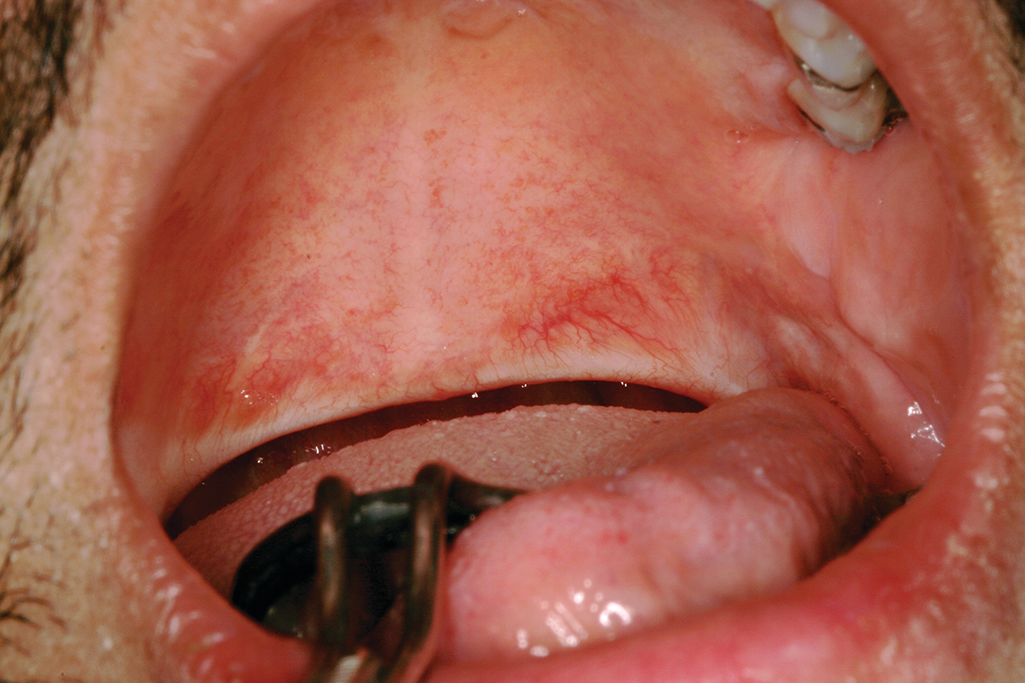

Answer Save 1 Answer Relevance mtwaites Lv 7 1 decade ago Favorite Answer You should talk with your doctor, and ask them to refer you onto a specialist that will reconstruct the palate region of your son This. We have known about the bifid uvula in connection with cleft palate cases for some time, yet some authors have reported no known functions for the uvula in decades past (figure 1) 1,2 Figure 1 Bifid uvula Photo courtesy of Dr Carolyn Bentley Research in the past few years has highlighted the importance of the uvula in speech patterns. What kind of problems may he have in future?Can he talk?.

The Uvula Conditions That Dental Hygienists Can Observe During An Exam Today S Rdh

The Uvula What Dental Hygienists Need To Know Registered Dental Hygienist Rdh Magazine